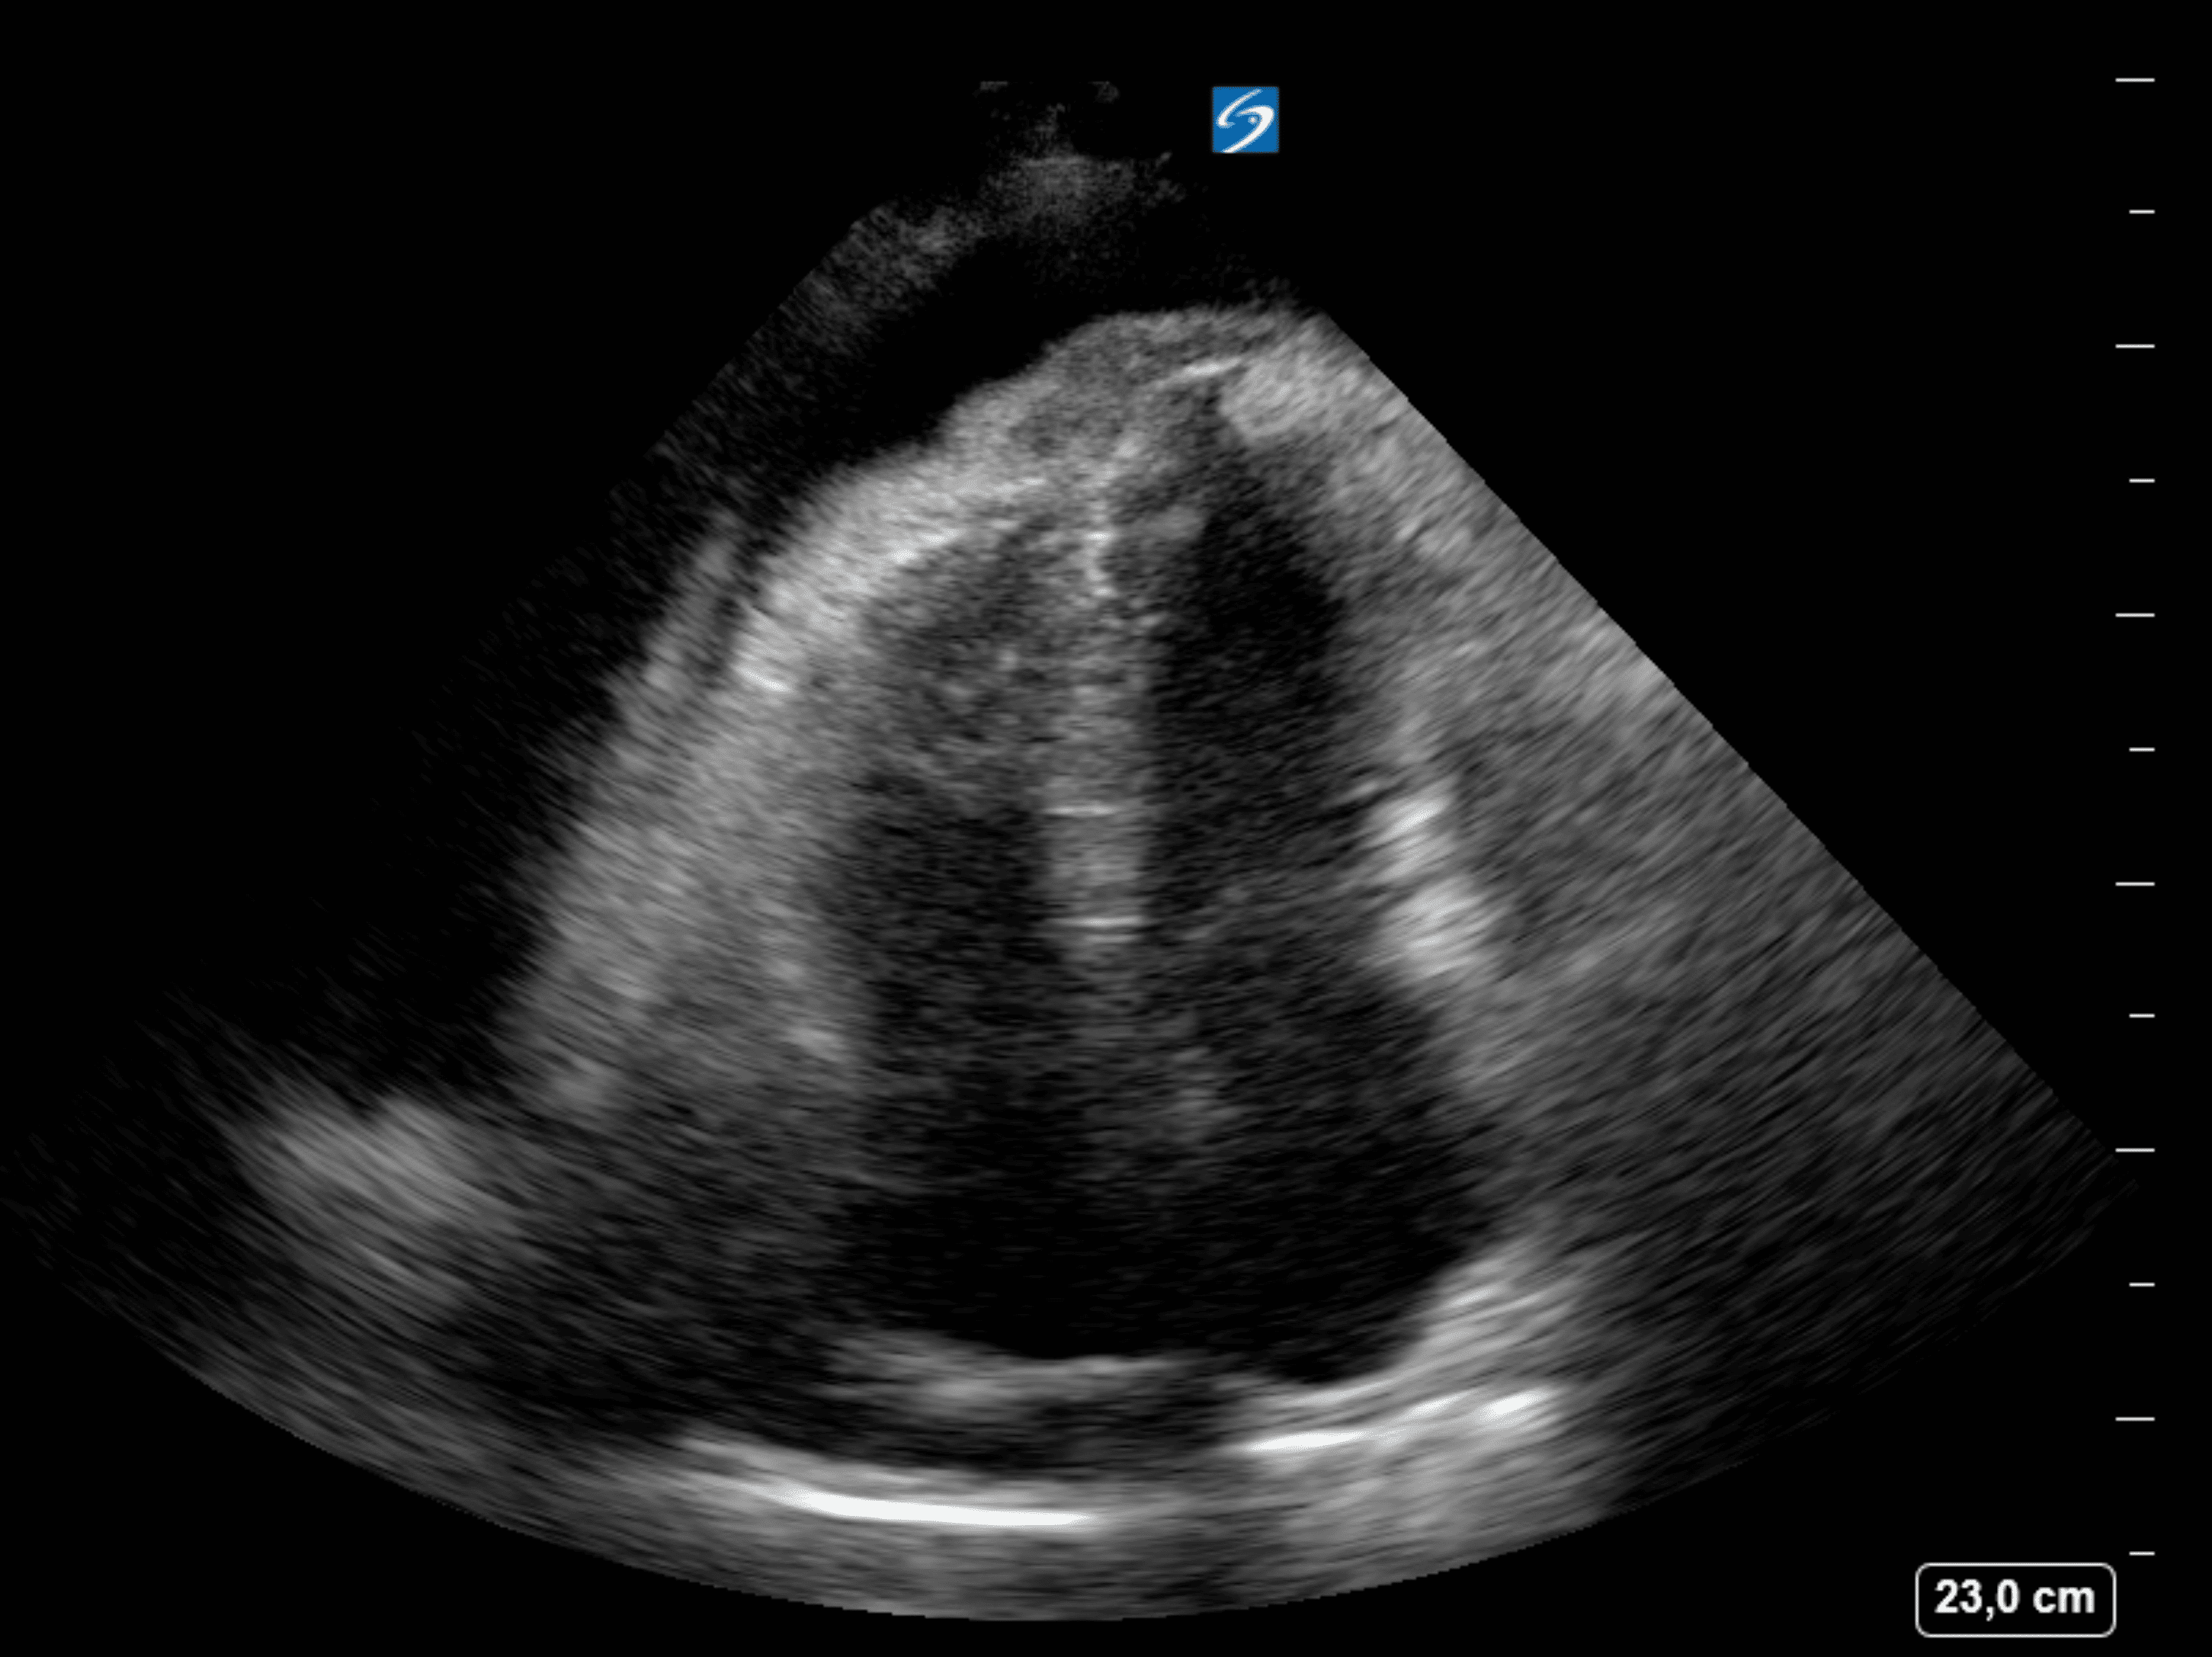

Se canaliza vía periférica para extracción de AS (x4), se administra SSF 500 ml iv. En urgencias se realiza un ecocardiograma EcoTT donde se visualiza un derrame pericárdico masivo, de hasta 6 cm a nivel inferior, circunferencial y con fibrina/implante a nivel del pericardio. Datos de colapso de cavidades derechas, swinning heart, variación de flujo transmitral 40% y TT 50%. VC dilatados, con colapso disminuido. Función biventricular normal.